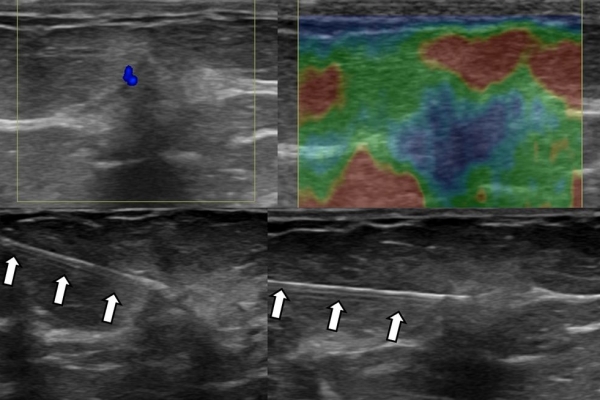

- Παρακέντηση με λεπτή βελόνη - FNA (fine needle aspiration). Είναι η απλούστερη επεμβατική μέθοδος βιοψίας μαστού. Υπό συνεχή υπερηχογραφική καθοδήγηση εισάγεται μια λεπτή βελόνη εντός του ύποπτου ευρήματος και αναρροφάται το περιεχόμενο, το οποίο μπορεί να δοθεί για κυτταρολογικό έλεγχο και/ή καλλιέργεια σε υποψία φλεγμονής.Είναι γρήγορη και είναι πολύ καλά ανεκτή χωρίς επιπλοκές. Η μέθοδος εφαρμόζεται:

- σε συμπτωματικές κύστεις για ανακούφιση από τα συμπτώματα

- Σε ύποπτη κύστη, δηλ μια “κύστη” χωρίς τυπική υπερηχογραφική απεικόνιση

- σε απόστημα μαστού